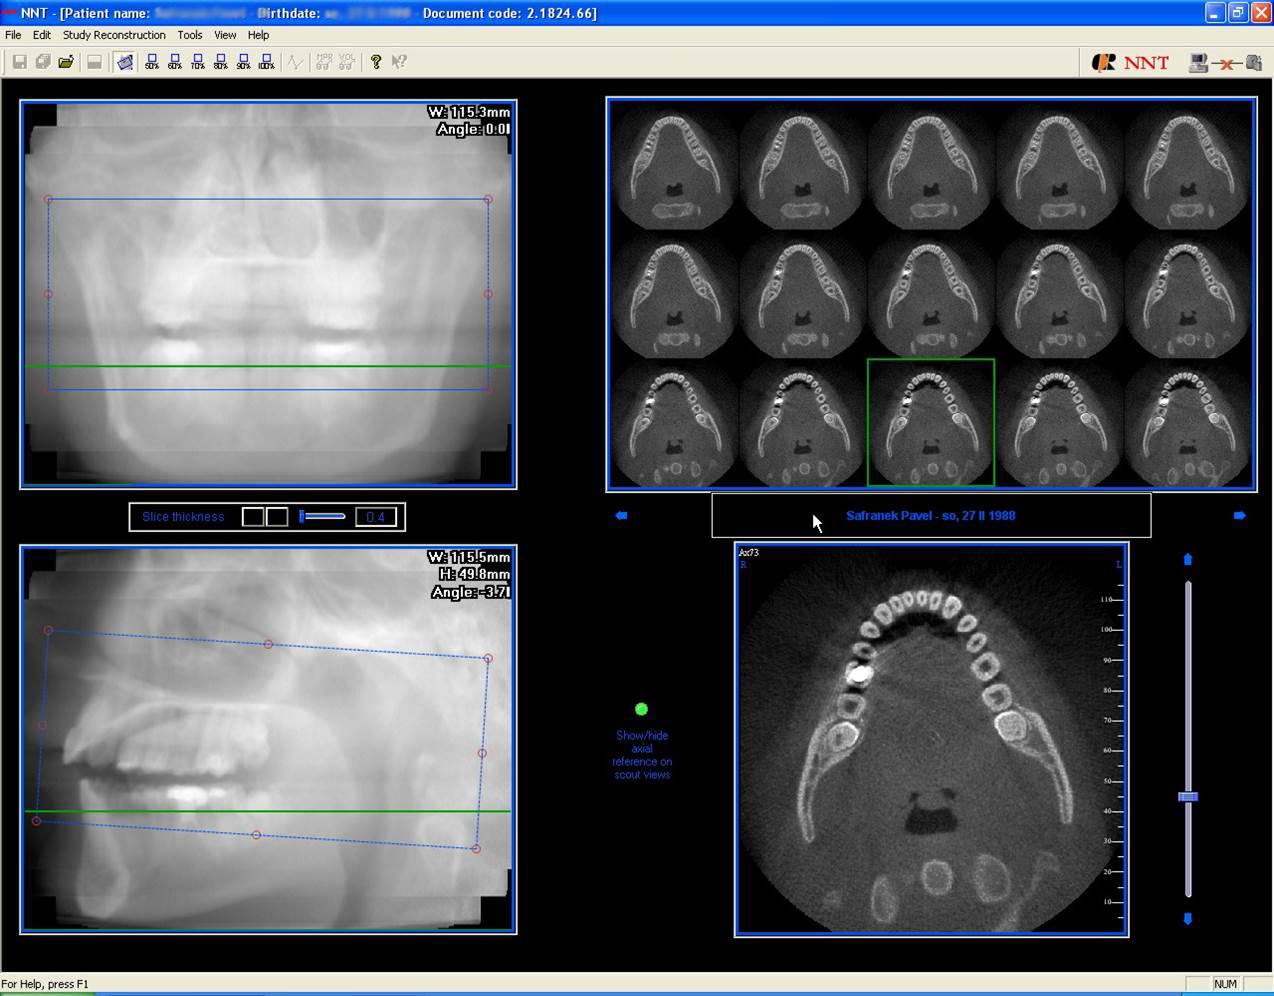

3D DVT - NewTom

Je speciální zubní digitální tříprostorový tomograf (3D), který umožňuje na základě jediného

snímkování vytvořit všechny typy RTG zobrazení, které jsou pro lékaře potřebné. Díky používané technologii tzv. „kuželového paprsku“ a speciálním senzorům je

výrazně zmenšená dávka záření - o více jak 80% proti klasickému CT vyšetření. To je významné zejména u dětí. Pomocí tohoto přístroje je možné zjisti skutečnou situaci v čelistních kostech pacienta tedy množství kosti - můžeme změřit skutečnou šířku i výšku kosti, i kvalitu kosti (hustotu) v místě uvažované implantace. 3D (tříprostorové) zobrazení umožňuje zvýšit prostorovou představu operatéra ještě před vlastní operací a zároveň pacientovi lépe objasnit a ukázat oblast plánovaného zavedení implantátu.

Pacient „neumí číst“ RTG snímky, ale díky 3D zobrazení vidí „svoji skutečnou čelist“

- např. jak je nízká či úzká, vidí průběh nervu nebo velikost čelistní dutiny, což mu umožní i pochopení nutnosti v některých případech provést pomocné zákroky ještě před vlastním zavedením implantátu (viz. kostní štěp, sinus lift, kostní granulát...).

Vyšetření pomocí tohoto přístroje používáme i ve stomatochirurgii (zlomeniny čelistí, zuby moudrosti, cysty, onemocnění čelistního kloubu), ortodoncii (retinované zuby, nadpočetné zuby), parodontologii atd.

NewTom Giano

Jedná se o nejnovějším přístroj ze skupiny dentálních hybridních CBCT (3D) + 2D (pan i ceph) systémů. Opět umožňuje na základě jediného snímkování vytvořit všechny typy RTG zobrazení, které jsou pro lékaře potřebné. Používaná technologii tzv. „kuželového paprsku“ a speciální senzory pro minimální zátěž při snímkování pacienta.

Vyšetření pomocí tohoto přístroje (nebo

3D DVT - NewTom) a získaná data používáme

pro každou implantaci, dále ve stomatochirurgii (zlomeniny čelistí, zuby moudrosti, cysty, onemocnění čelistního kloubu), ortodoncii (retinované zuby, nadpočetné zuby), parodontologii atd.